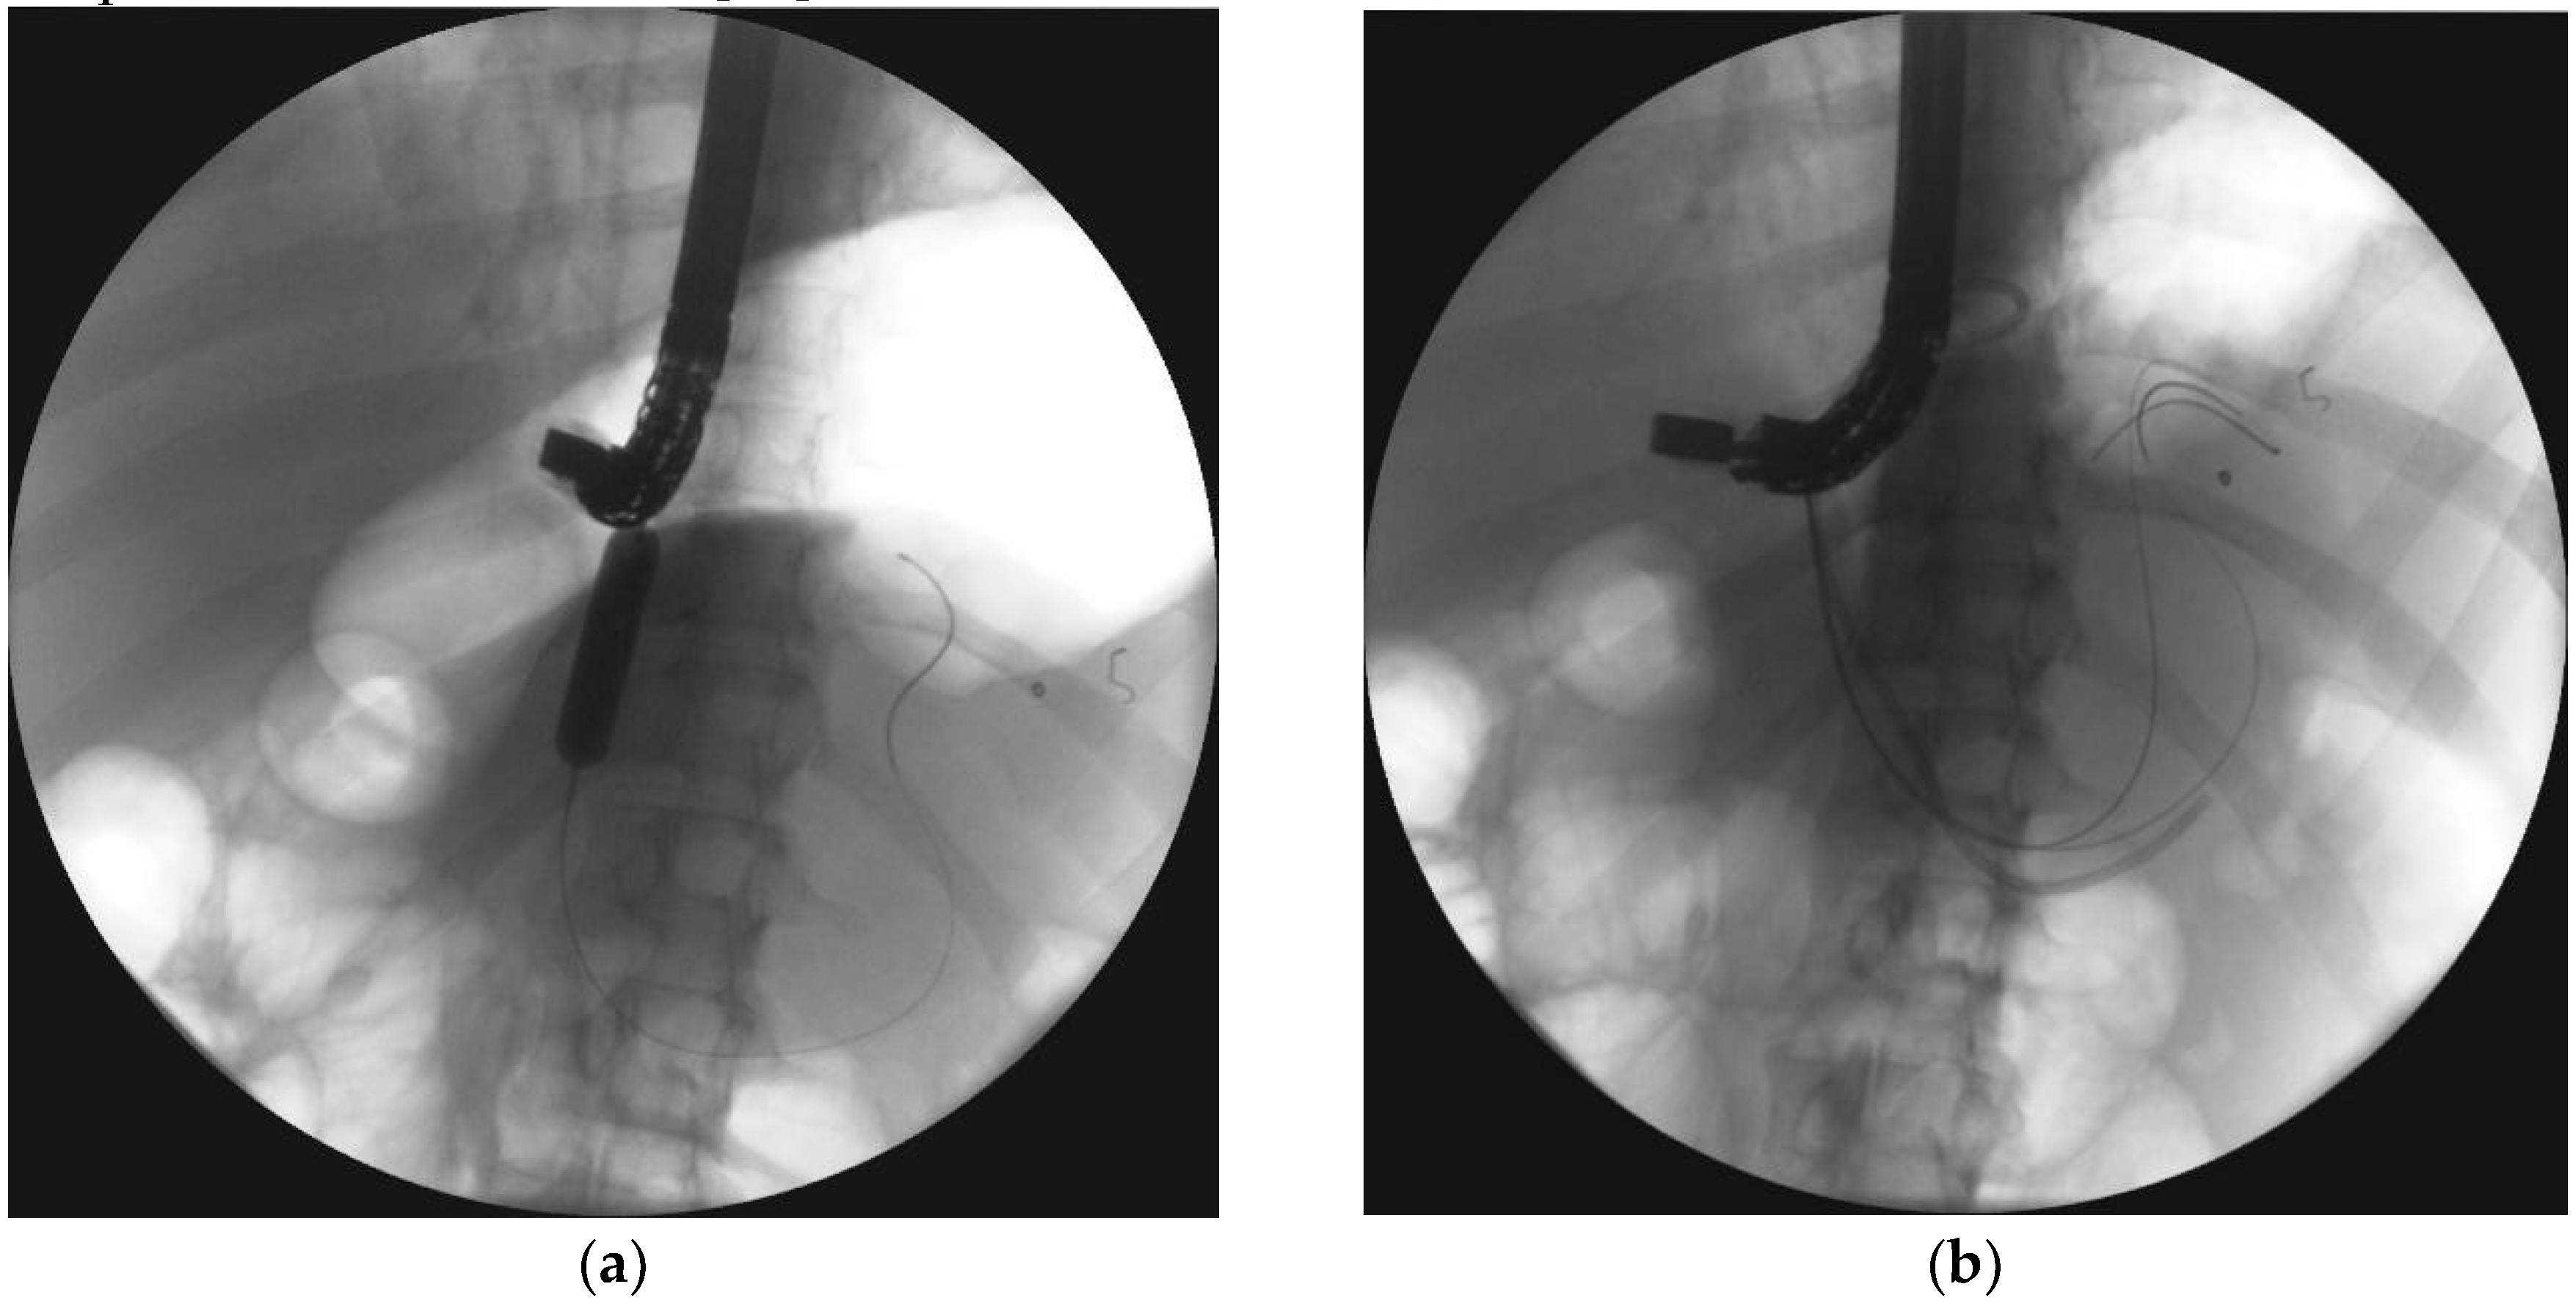

- Jagielski, M.; Smoczyński, M.; Adrych, K. Transpapillary drainage of pancreatic parenchymal necrosis. Wideochir. Inne. Tech. Maloinwazyjne 2015, 10, 491–494. [Google Scholar] [CrossRef]

- Smoczyński, M.; Jagielski, M.; Siepsiak, M.; Adrych, K. Endoscopic necrosectomy through the major duodenal papilla under fluoroscopy imaging. Arch. Med. Sci. 2018, 14, 470–474. [Google Scholar] [CrossRef] [PubMed]